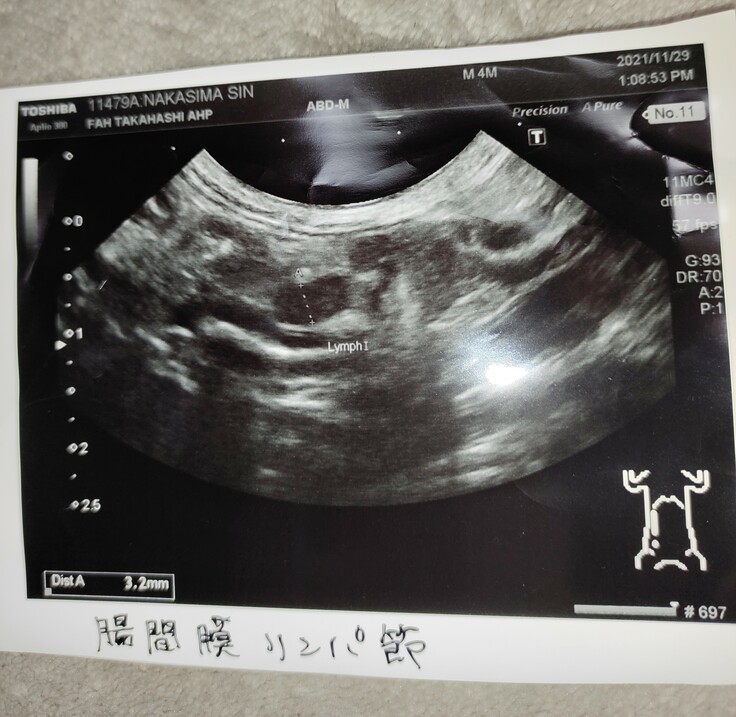

③エコー写真(腸間膜のリンパ節の様子)

エコー検査では、内蔵や腸に関してはリンパ腫れておらず(3.2mmはギリギリセーフ)、腹水も溜まってないとの状況でした。これらの結果により、ウェットタイプや、ウェットとドライを持ち合わせた中間型タイプの確率は消えました。